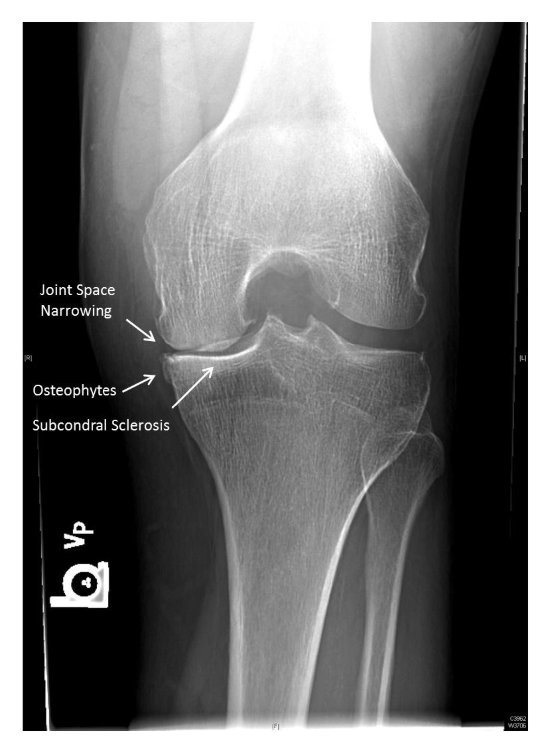

3 key radiographic features of OA?

If all 3 of these findings are not present, another diagnosis should be considered.

X-ray of joint space narrowing

what is sclerosis?

What is osteophytosis?